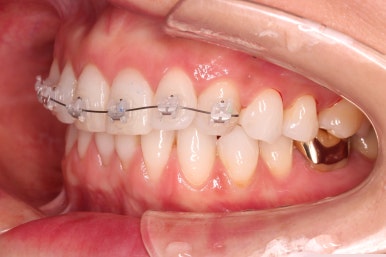

윗니에만 장치를 부착하고 부분교정을 시작했습니다.

환자분이 연산동부분교정 선택하신 장치는 엠파워 클리어라고 하는 자가결찰 세라믹 장치입니다.

장치 부착한 모습 참고해 주시고요.

적절하게 치간삭제를 일부 동반하여 빠른 시일 내에 가지런하게 해드리고 마무리를 했습니다.

환자분이 원하시는 만큼 가지런해졌고, 부가적으로 생길 수 있는 부분들도 수용 가능한 선에서 잘 마무리가 되었습니다.

3개월이라는 빠른 기간 내에(심미보철 보다 약간만 더 긴 시간) 치아의 손상없이 마무리를 잘 했습니다.